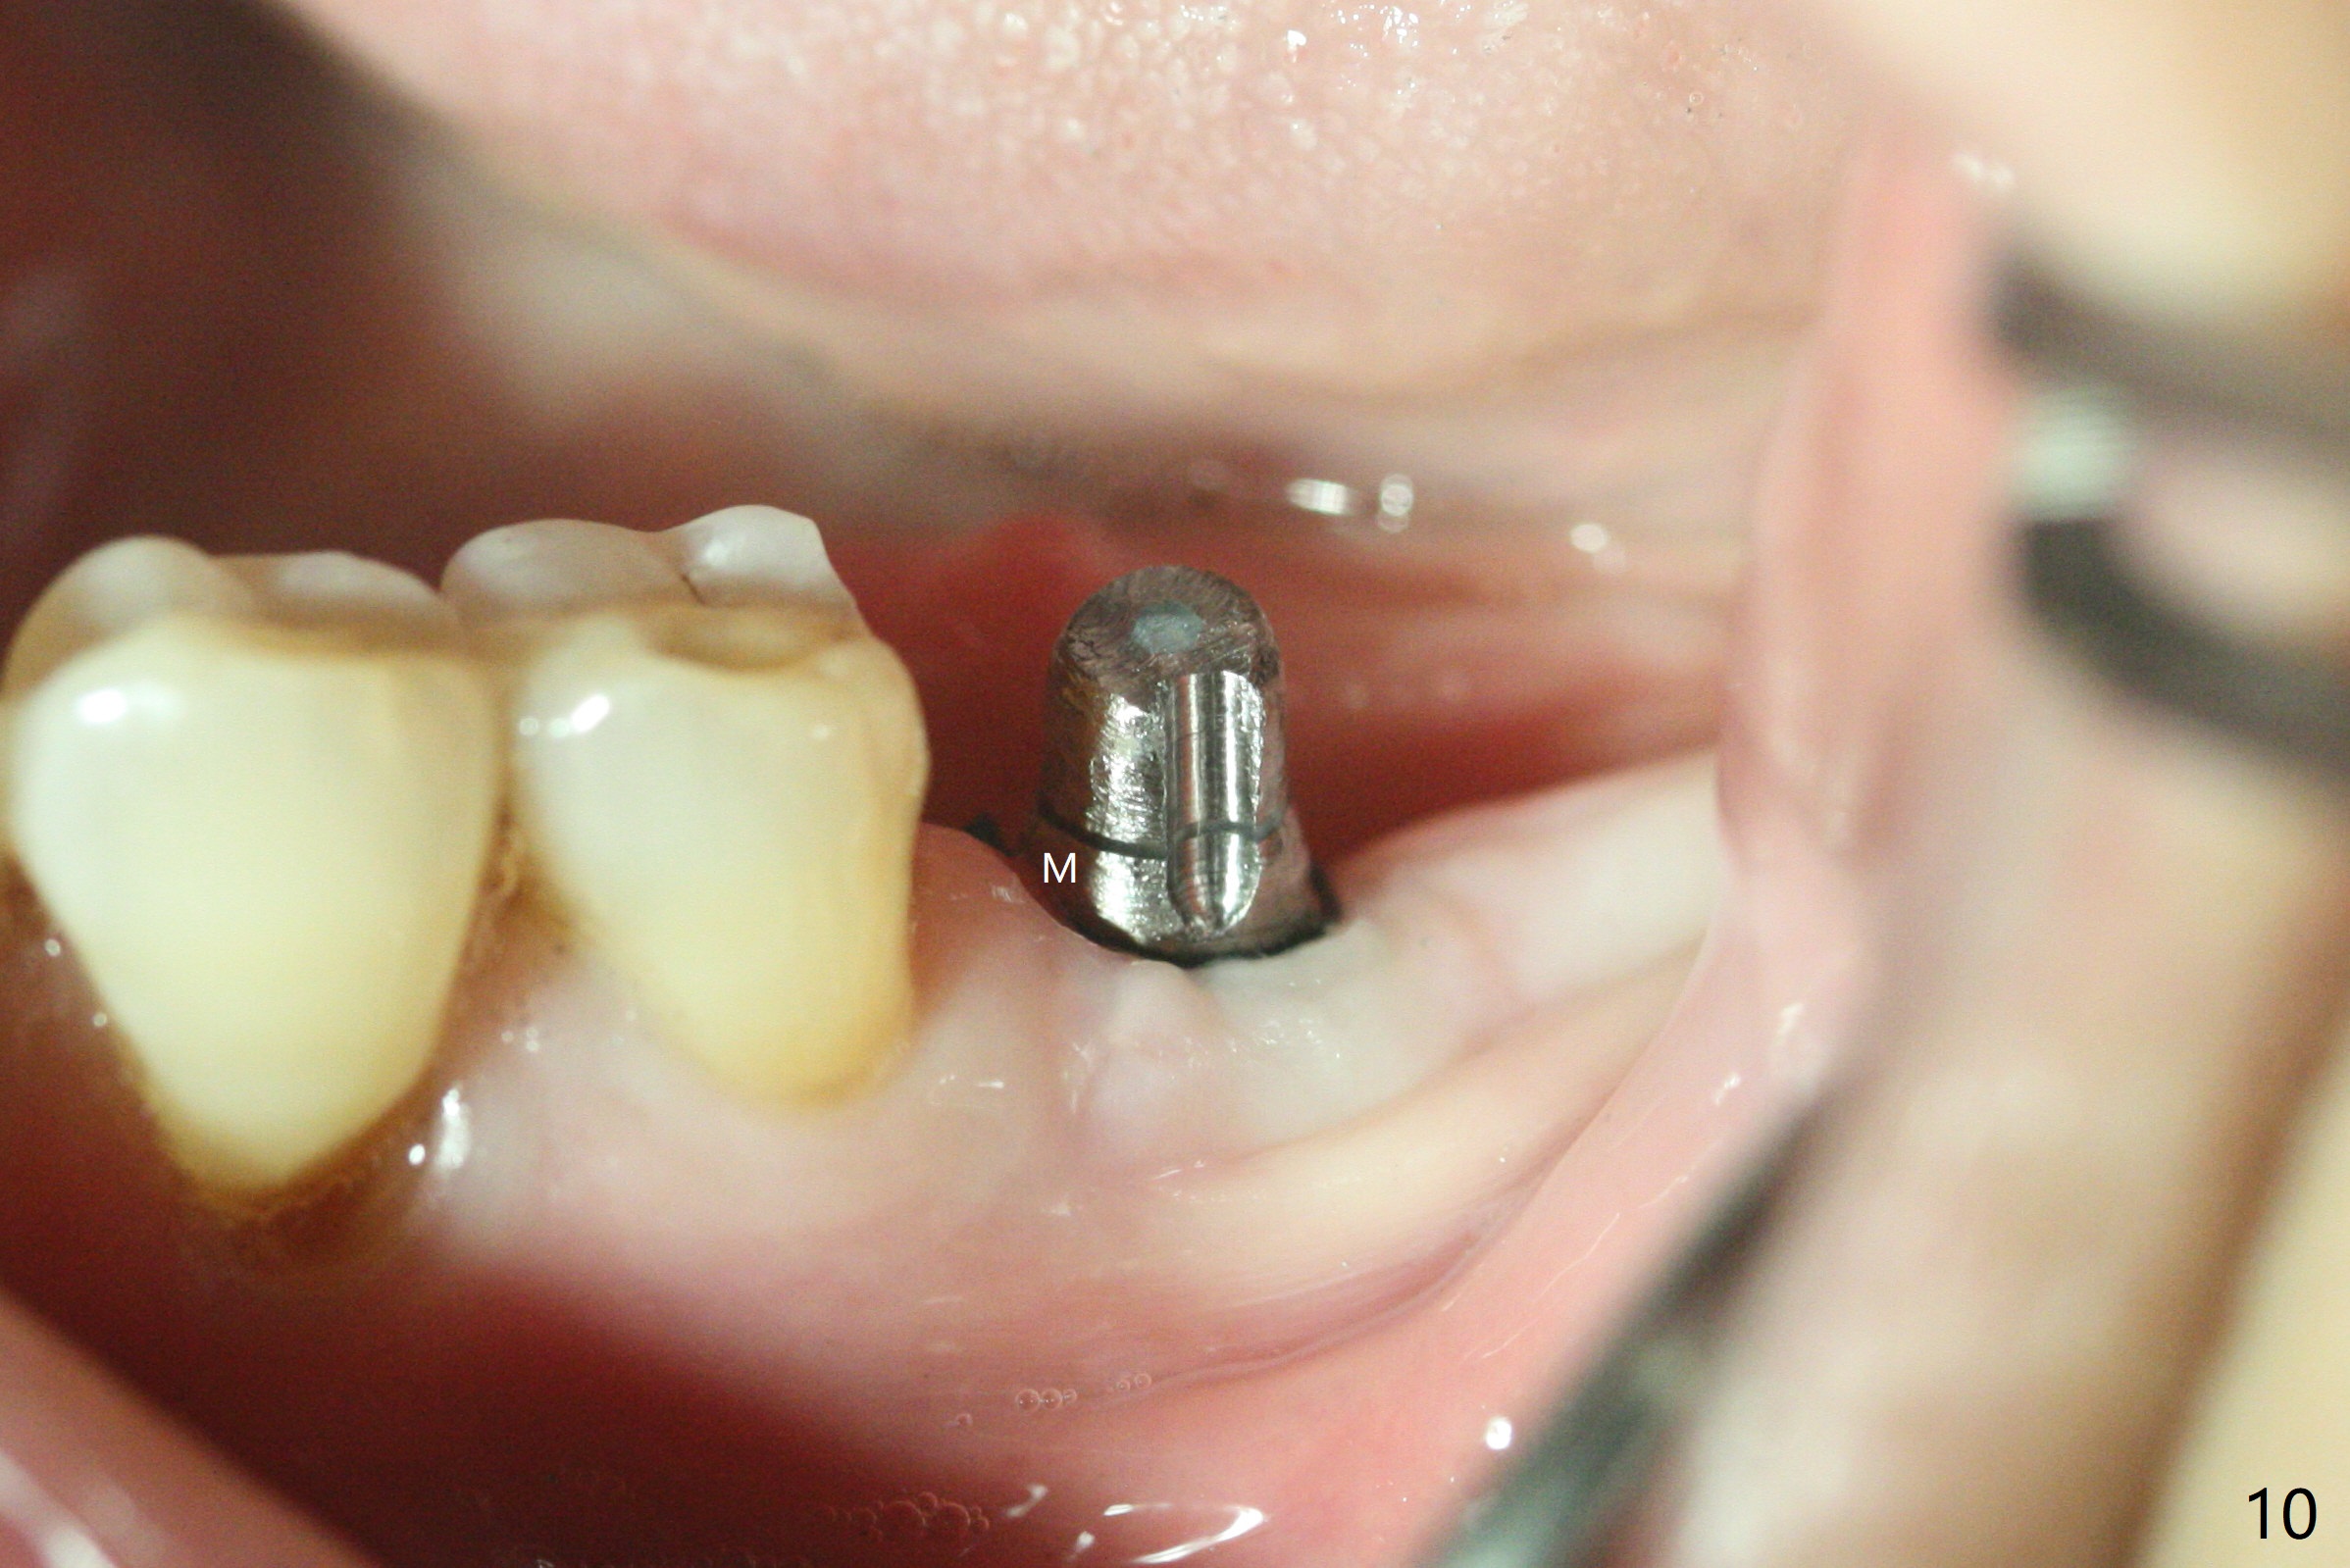

Apical 3 mm Underdrill Post Cortical Drill M

Following light use of 4 mm tissue punch, a buccal incision is made and raised. After 4x8.5 mm drill with 10.5 mm offset at #19, 4.5 mm cortical drill is used for 2/3 length to take care of the thick dense lingual plate (overprep). The remaining apical 3 mm osteotomy is underdrill (3.5 mm). After try-in of a 4.5x14 mm tissue-level dummy implant, a same-sized definitive one obtains 35 Ncm torque (Fig.1). Following 3-4 more turns, the torque reaches 45 Ncm (Fig.2) with the distal thread covered (<) and autogenous bone graft placed in the distal defect (*). A 4x3 mm unipost is placed to keep periodontal dressing in place. Clinically the implant is placed within bone boundary buccolingually. The new implant seems necessary considering short (Fig.2 S) and probably resorbed (Fig.1 R) roots of the premolars. In fact the short abutment keeps the mesiolingual portion of periodontal dressing for 2 weeks; since local hygiene is suboptimal, the healing screw is placed after abutment and dressing removal (Fig.3).